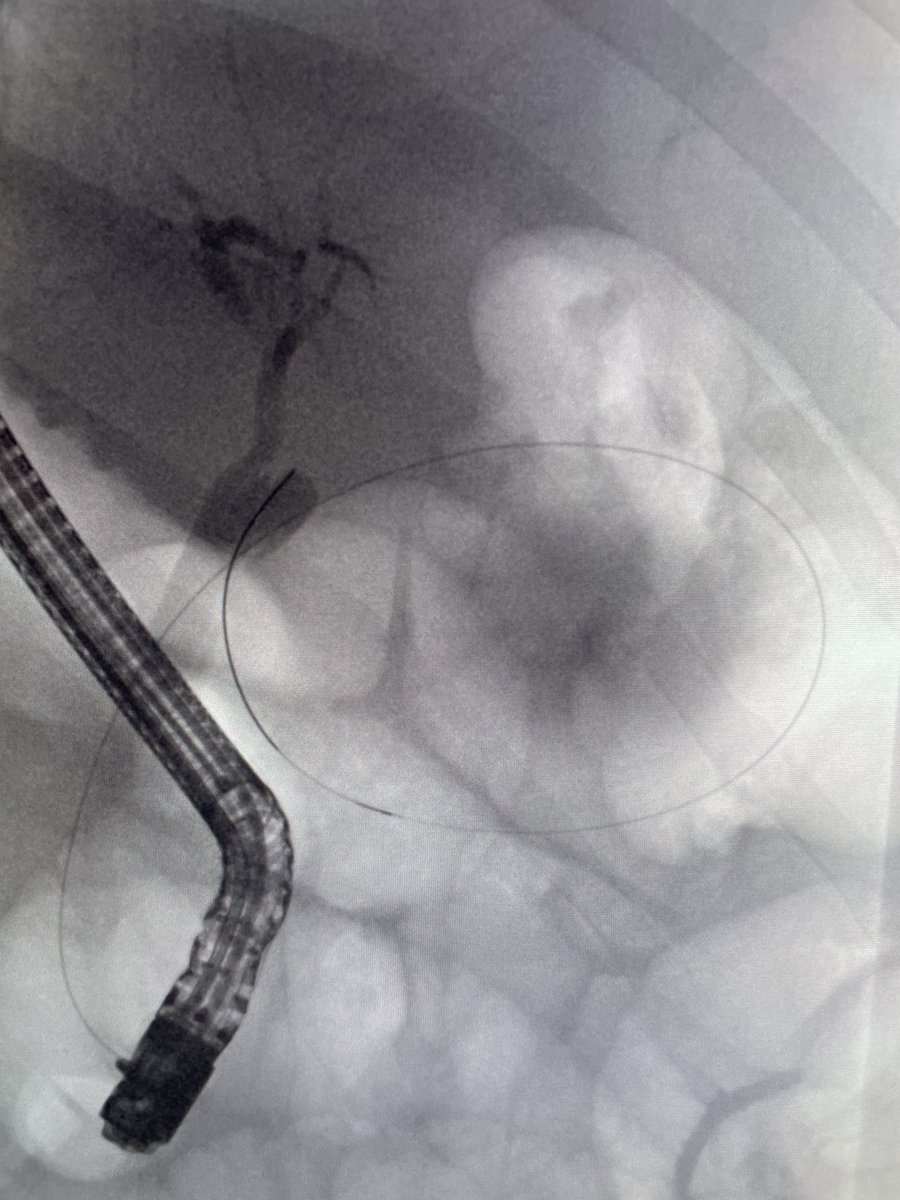

Gastroenterology, Gastrointestinal Endoscopy, Médico Gastroenterólogo en Hospital Nacional Dos de Mayo HNDM, Twitter (X): Publicaciones solo opiniones.

Agradecidos y orgullosos por este reconocimiento a un hospital peruano 🇵🇪 Prometemos estar a la altura y la experiencia será genial para todos. Gracias por la gestión @KatiaHernandezT y a estos cracks que son parte del team: @Jegaso28 @isgvich Gracias @ISNkidneycare